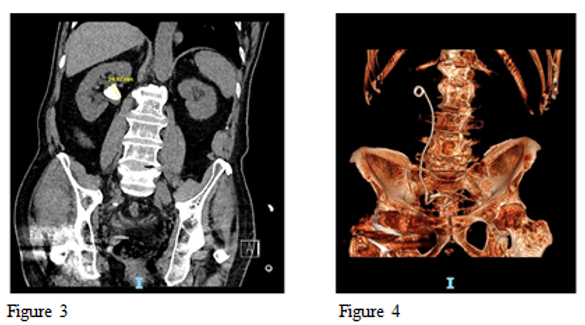

Figure 3 Pre op Large renal pelvic stone 24mm and Figure 4 Post op 3d reconstructed CT scan showing complete clearance of the stone after single procedure using High Power Holmium Laser.